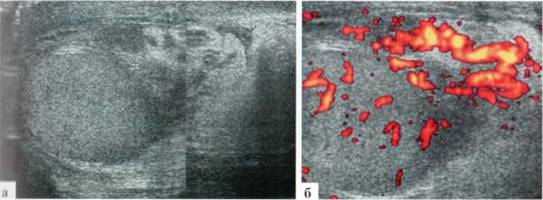

Орхит у детей встречается редко, чаще в подростковом возрасте, но зафиксирован и у новорожденных. Причина заболевания не всегда ясна, клинико-лабораторное подтверждение инфекции мочевыводящих путей, которой отводится известная роль в генезе орхитов и эпидидмитов, имеет место далеко не всегда. Характерны весьма разнообразные изменения структуры яичка в В-режиме: от редко выраженных до практически не дифференцируемых. В большинстве случаев имеет место некоторое увеличение яичка в размерах, преимущественно — в толщину, при этом оно приобретает шаровидную форму. Эхогенность паренхимы может оставаться нормальной, может диффузно понижаться. Всегда имеется значительное усиление сосудистого рисунка в паренхиме яичка. Часто определяется некоторое снижение RI артериального тестикулярного кровотока, но, строго говоря, количественная оценка тестикулярного кровотока при гиперемии яичка у детей с орхитами редко дает принципиально новую информацию для оценки состояния пораженного органа. Часто определяется утолщение оболочек яичка за счет их отека и небольшое количество жидкостного содержимого в оболочках (рис. 2.3.1).

Рис. 2.3.1. Орхит слева у ребенка 11 лет: а, б — правое неизмененное яичко 32x15 мм; в, г — левое яичка увеличено в размерах до 42x26 мм, паренхима гомогенная, без значительных структурных изменений, резко выраженное диффузное усиление сосудистого рисунка

Весьма демонстративным является поперечное сканирование мошонки, когда датчик располагается перпендикулярно ее шву, и в поле сканирования попадают одновременно оба яичка или хотя бы их внутренние фрагменты. Изменение формы яичка и интенсивности интратестикулярного сосудистого рисунка не вызывают сомнения (рис. 2.3.2).

Рис. 2.3.2. Поперечное сканирование по передней поверхности мошонки у ребенка 13 лет с правосторонним орхитом с одновременной визуализацией фрагмента правого (D) и левого (S) яичек